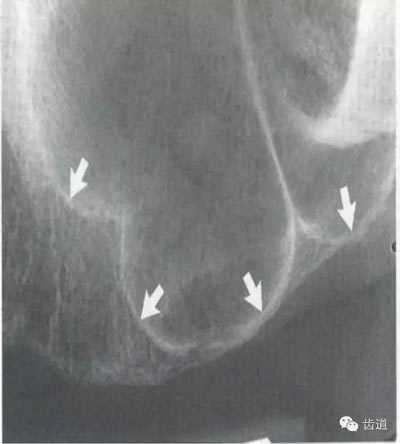

在投照上頜磨牙根尖片時,經(jīng)??梢钥吹窖栏戏接幸幻芏鹊偷挠跋?,為上頜竇的一部分,邊緣環(huán)繞以密度高的線狀影像,為上頜竇壁致密骨層。有時可見上頜竇的分隔。